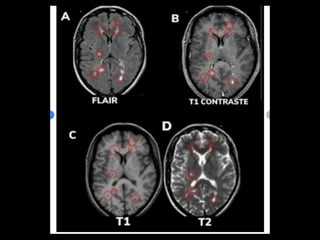

critérios  McDonald  (2017)   • disseminação  no  espaço   – RM  por  ≥  1  lesões  hiperintensas  em  T2,   sintomá+cas  ou  assintomá+cas,  que  são   caracterís+cos  de  EM,  em  dois  ou  mais  das   seguintes  quatro  áreas  do  sistema  nervoso   central:     • periventricular,     • cor+cal/justacor+cal,  infratentorial  e  medula  espinhal.

• disseminação  no  tempo   – presença  simultânea  de  lesões  captantes  de   gadolíneo  e  lesões  não  captantes  em  qualquer   exame  de  RM,     – ou  nova  lesão  hiperintensa  em  T2  ou  captante  de   gadolínio  quanto  comparada  a  um  exame  de  RM   prévio,  independentemente  do  momento  em  que   foi  realizado.

Diagnóstico:   Observação: ARM pode evidenciar áreas com pontos brilhantes indefinidos em indivíduos saudáveis; Gadolínio: • realçar lesões, • destacar se a doença está em estado ativo